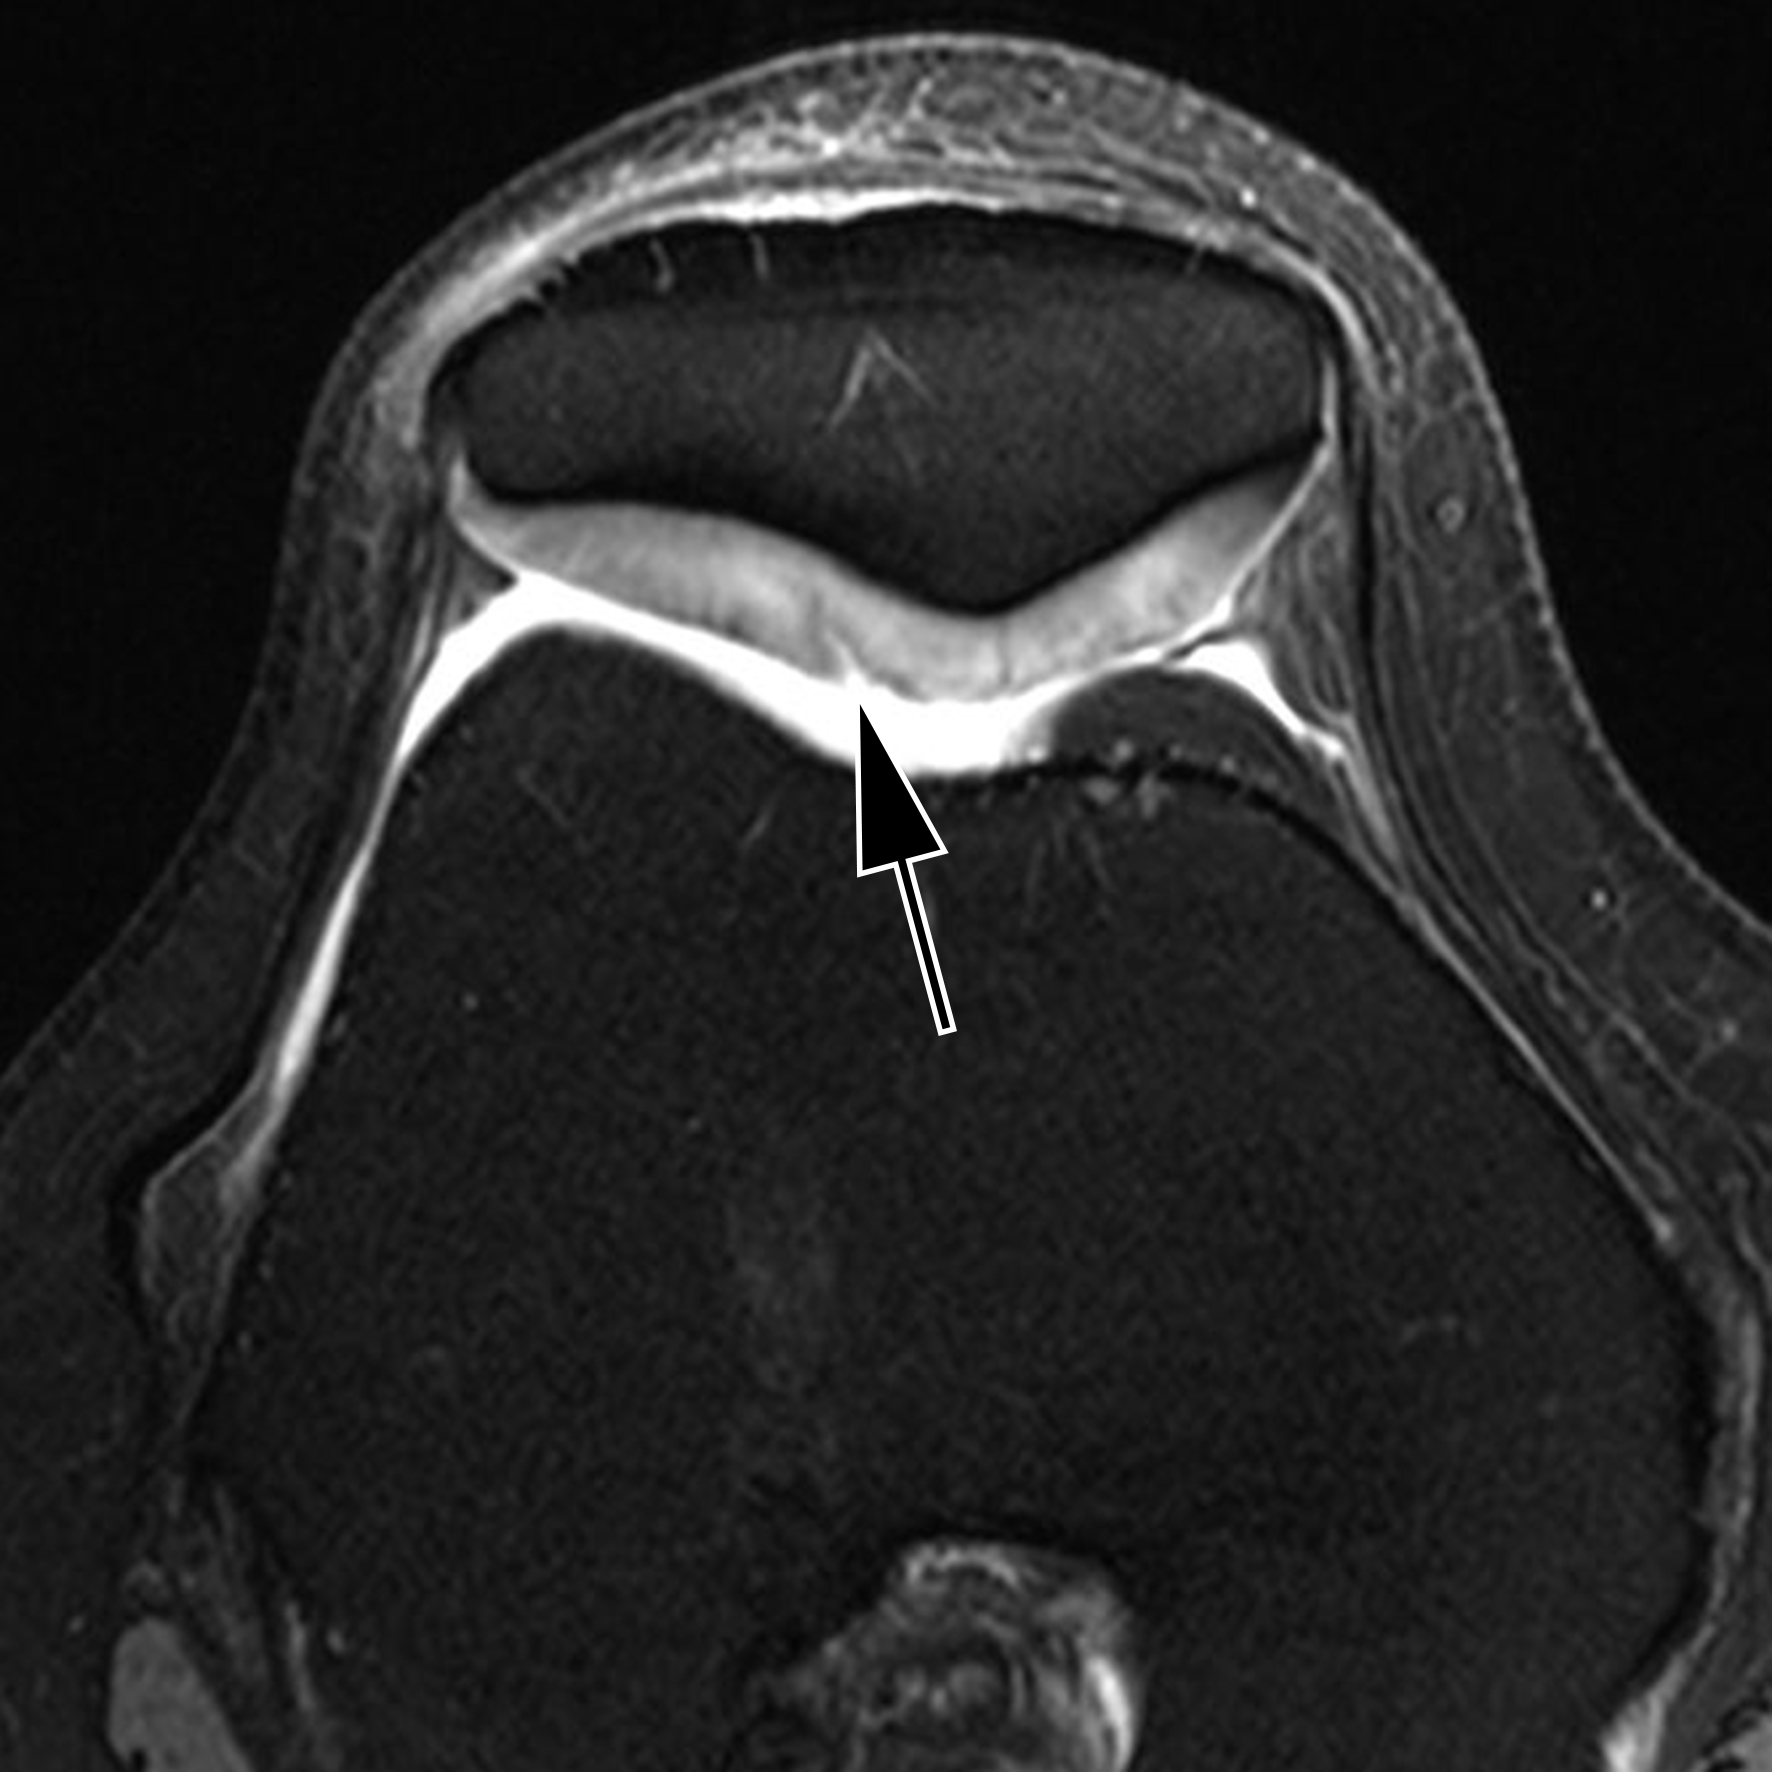

„Der neue MRT ermöglicht dank der sehr hohen Auflösung detaillierte Einblicke in den menschlichen Bewegungsapparat, zeigt präzise die Stoffwechselprozesse im Gehirn und hilft außerdem bei der Darstellung neurologischer Krankheiten“, sagt Prof. Dr. Michael Uder, Direktor des Radiologischen Instituts des Universitätsklinikums Erlangen. Für seinen Kollegen, Prof. Dr. Arnd Dörfler, Leiter der Neuroradiologischen Abteilung des Universitätsklinikums Erlangen, zeigt der neue MR-Scanner besonders bei Gehirnuntersuchungen seine Vorteile: „Bei 7-Tesla sind Gehirnschädigungen dank der besseren Auflösung und des deutlich stärkeren Bildkontrasts viel klarer zu erkennen.“ Anwendungsbeispiele hierfür seien Multiple Sklerose, Hirntumoren oder Metastasen, Epilepsie und Demenz, bei denen die höhere Detailauflösung neue diagnostische Möglichkeiten bietet, die bei niedrigeren Feldstärken so nicht möglich wären. „Viele Erkrankungen können so wahrscheinlich besser und schneller erkannt und damit effektiver behandelt werden“, so Prof. Dörfler

Der Grund für die bessere Auflösung der Untersuchungsbilder ist die höhere Messgenauigkeit des neuen Systems. Diese hängt mit der Feldstärke des Magneten im MRT zusammen. Je stärker das Magnetfeld ist, je genauer ist die Bildgebung. Da die Feldstärke am 7-Tesla-MRT mehr als doppelt so hoch ist, wie die der heute gebräuchlichen 3-Tesla-MRT, können nicht nur feinste Gewebestrukturen besser sichtbar gemacht werden, sondern auch Stoffwechselprozesse im Gewebe. Am Standort Erlangen werden die Möglichkeiten des neuen Ultrahochfeld-MRT jetzt intensiv weiter erforscht.